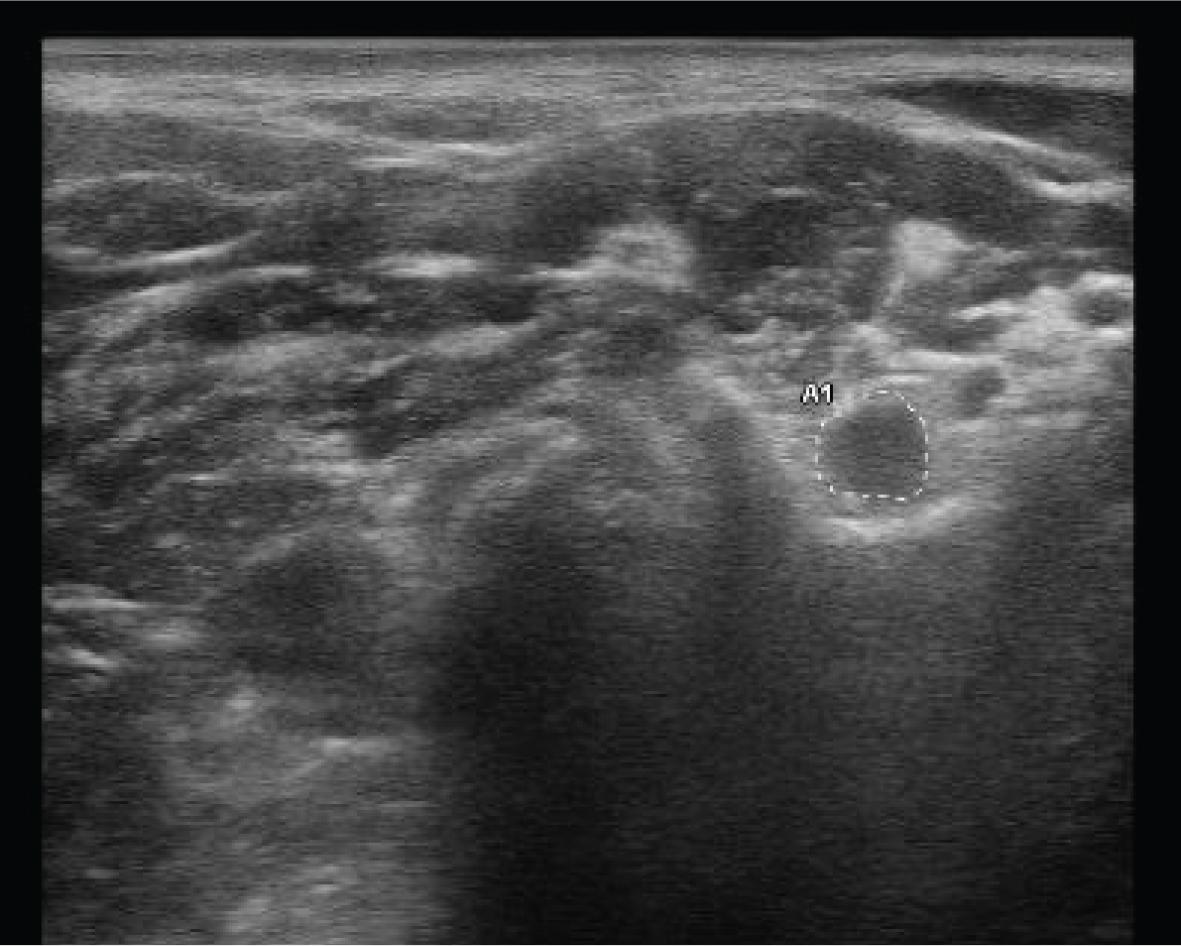

However, the development of a special, very precise sense of endpoint of the tension of the nervous system elements and the knowledge regarding phases this technique may be used in (which requires certain experience) is the basis for efficient neuromobilisation. This leads to the fact that, surprisingly, the results of the therapy vary from spectacular pain reduction to an increase in pain and paraesthesia symptoms. Excessive stimulation of the nervous tissue with inflammatory oedema without removing an obstacle is a highly probable cause of this. In this case, a quick USG diagnosis (fig. 4) makes it possible to assess the degree of nerve or root oedema and avoid mistakes by reducing the oedema in the first phase (unblocking the lymphatic drainage ducts, broadening border sphere for the nervous tissue) and performing mobilisation in the next phase (fig. 5).

USG image of the oedematous root of brachial plexus – measurement of the area at the level of the transverse process